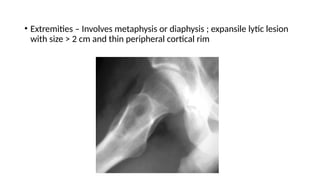

• Extremities – Involves metaphysis or diaphysis ; expansile lytic lesion

with size > 2 cm and thin peripheral cortical rim